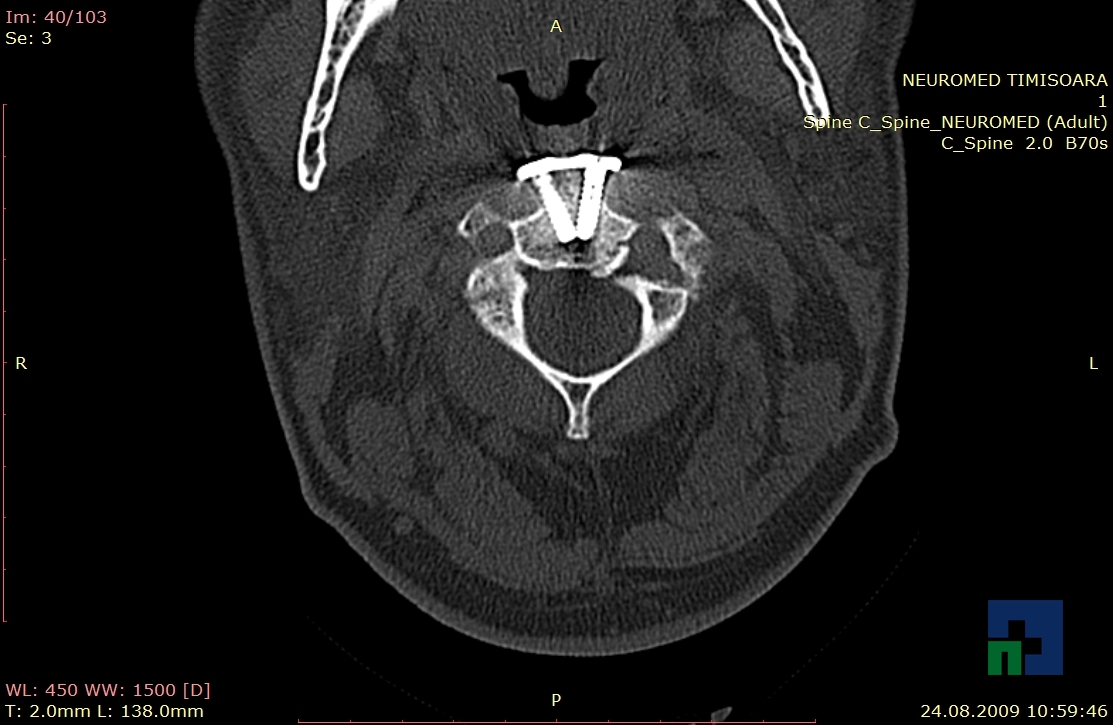

- Diagnosticul fracturilor:

- Unice

- Multiple

- Cu înfundare

- Complexe cranio-sinusale

- Complexe cranio-etmoidale

- Complexe cranio-orbitare

- Complexe cranio-faciale